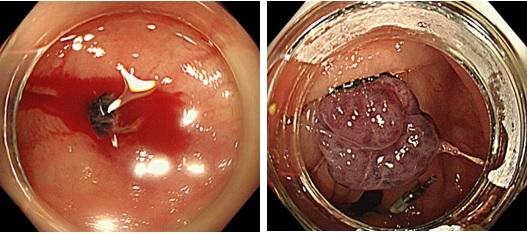

③消化管出血

内視鏡的消化管止血術

出血性胃潰瘍、十二指腸潰瘍、大腸憩室出血、直腸潰瘍などの内視鏡的止血処置を多数行っております。ほぼ全例、内視鏡で止血が完了しますが稀に止血困難の際には放射線治療科と連携しカテーテル治療も速やかに行える体制を取っております。

出血性胃潰瘍に対する凝固止血

大腸憩室出血に対するEBL(バンド結紮術)

内視鏡的静脈瘤結紮療法(EVL)・静脈瘤硬化療法(EIS)

食道・胃静脈瘤破裂に対して内視鏡を使ってゴムバンドで結紮、止血します。破裂予防として硬化剤を血管内に注入し静脈瘤を消失させることもあります。

食道静脈瘤破裂に対するEVL